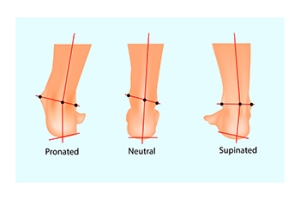

The Dangers of Excessive Supination

Supination, or underpronation, occurs when your body weight shifts to the outer edges of your feet during walking or running. In a normal stride, your foot should gently roll inward, or pronate, distributing your weight evenly across the ball of the foot, and pushing off using the big toe. In supination, most of the weight is on the outer edge, with push-off from the outer toes. These faulty foot mechanics can have significant implications for overall health. Excessive supination can lead to issues such as back and hip pain, knee stress, ankle injuries, and heel pain. The abnormal weight distribution also increases the risk of chronic pain and injuries, and makes you more susceptible to ankle problems and other foot conditions. Supination can result from inherited structural problems in the foot, like high arches. Weakness in the muscles of the foot, ankle, and leg can also contribute. Footwear that lacks sufficient support, body misalignment, or prior foot injuries that have damaged tendons or muscles can also be factors. To address problems caused by excessive supination, it is suggested that you make an appointment with a podiatrist who can diagnose your structural foot problems, perform a gait analysis, and provide appropriate treatment options.

Biomechanics in Podiatry

Podiatric biomechanics is a particular sector of specialty podiatry with licensed practitioners who are trained to diagnose and treat conditions affecting the foot, ankle and lower leg. Biomechanics deals with the forces that act against the body, causing an interference with the biological structures. It focuses on the movement of the ankle, the foot and the forces that interact with them.